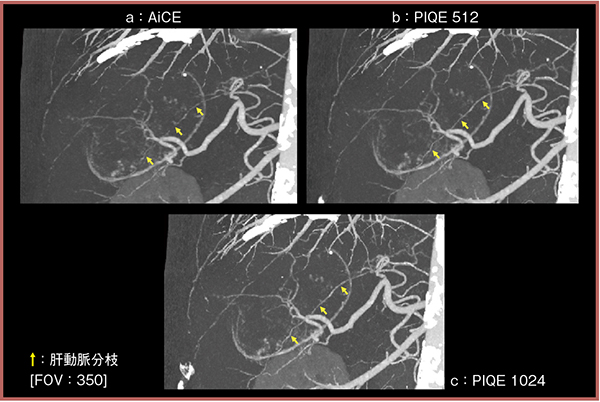

次に,実臨床画像でも視認性を比較した。80歳代,男性,造影CTにて後区域に巨大な低濃度不均一の腫瘤が認められ,肝細胞がんが疑われた症例である。腫瘤の栄養血管のMIP画像(図1)を比較したところ,PIQE(1024マトリクス:c)では血管が末梢まで連続性をもって描出されており,微細な血管構造も視認可能であった(↑)。

図1 実臨床画像におけるAiCEとPIQEの視認性の比較